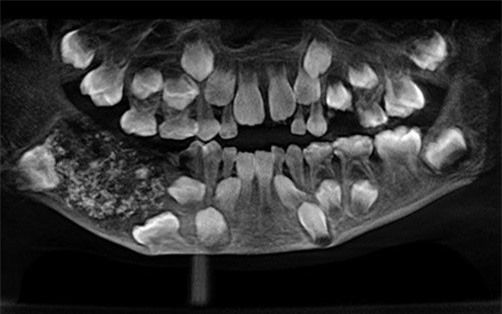

Old  Arrow Cậu bé Ấn có đến 526 cấu trúc giống răng

Một cặp bố mẹ đã đưa đứa con trai với hàm răng sưng tấy của mình đến Bệnh viện Đại học răng hàm mặt Saveetha ở Chennai, thủ đô bang Tamil Nadu do lo sợ cậu bé bị ung thư. Sau khi phát hiện các cấu trúc giống nang răng ẩn trong khắp hàm cậu bé, các bác sĩ đã tiến hành phẫu thuật và loại bỏ đến 526 cấu trúc giống như răng lớn nhỏ.

Cấu trúc giống răng của cậu bé. Ảnh:Saveetha Dental College and Hospital.

Các nhà nghiên cứu bệnh lý răng miệng kinh ngạc chia sẻ: “Có tổng cộng hơn 500 cấu trúc răng nằm trong hàm cậu bé 7 tuổi, giống như những viên ngọc trong một con trai”.

Theo nguồn tin từ bệnh viện, các bác sĩ đã mất đến 5 tiếng để loại bỏ toàn bộ các cấu trúc răng trong hàm cậu bé. Những cấu trúc răng có kích thước từ 1mm đến 15mm, mỗi mẩu răng đều được bao phủ bởi lớp men khá hoàn chỉnh.

Bệnh viện chữa trị cho biết: “Đây là trường hợp đầu tiên được ghi nhận trên toàn thế giới về hiện tượng kỳ lạ này, một người có từng ấy nang răng trong miệng. Bệnh lý hiếm gặp này có tên là “u răng đa hợp” (compound odontome).

Theo nghiên cứu của Học viện Nhi Nha khoa Mỹ, u răng đa hợp là sự phát triển bất thường khiến các khối u hình thành từ men răng được một lớp ngà răng bao phủ. Bệnh lý này thường được phát hiện ở những người trong độ tuổi 20 nhưng cũng có thể được chẩn đoán ở mọi lứa tuổi.

Năm 3 tuổi, cậu bé đã được bố mẹ đưa đi khám vì bị sưng hàm nhưng do cậu còn quá bé nên không chịu hợp tác với bác sĩ. Các vết sưng vẫn tiếp tục gia tăng khi cậu lớn lên. Bệnh viện vẫn chưa xác định chính xác thời điểm phẫu thuật cắt bỏ các nang răng để ngăn các u răng phát triển trở lại.

Bệnh viện nơi cậu bé điều trị cho biết: “Quyết định của bác sĩ loại bỏ tổn thương hoàn toàn thay vì khám phá nó trên bàn mổ (như mở một bọc giun) đã tránh được một tai nạn nghiêm trọng và tránh cho bệnh nhân không phải gây mê trong thời gian dài”.